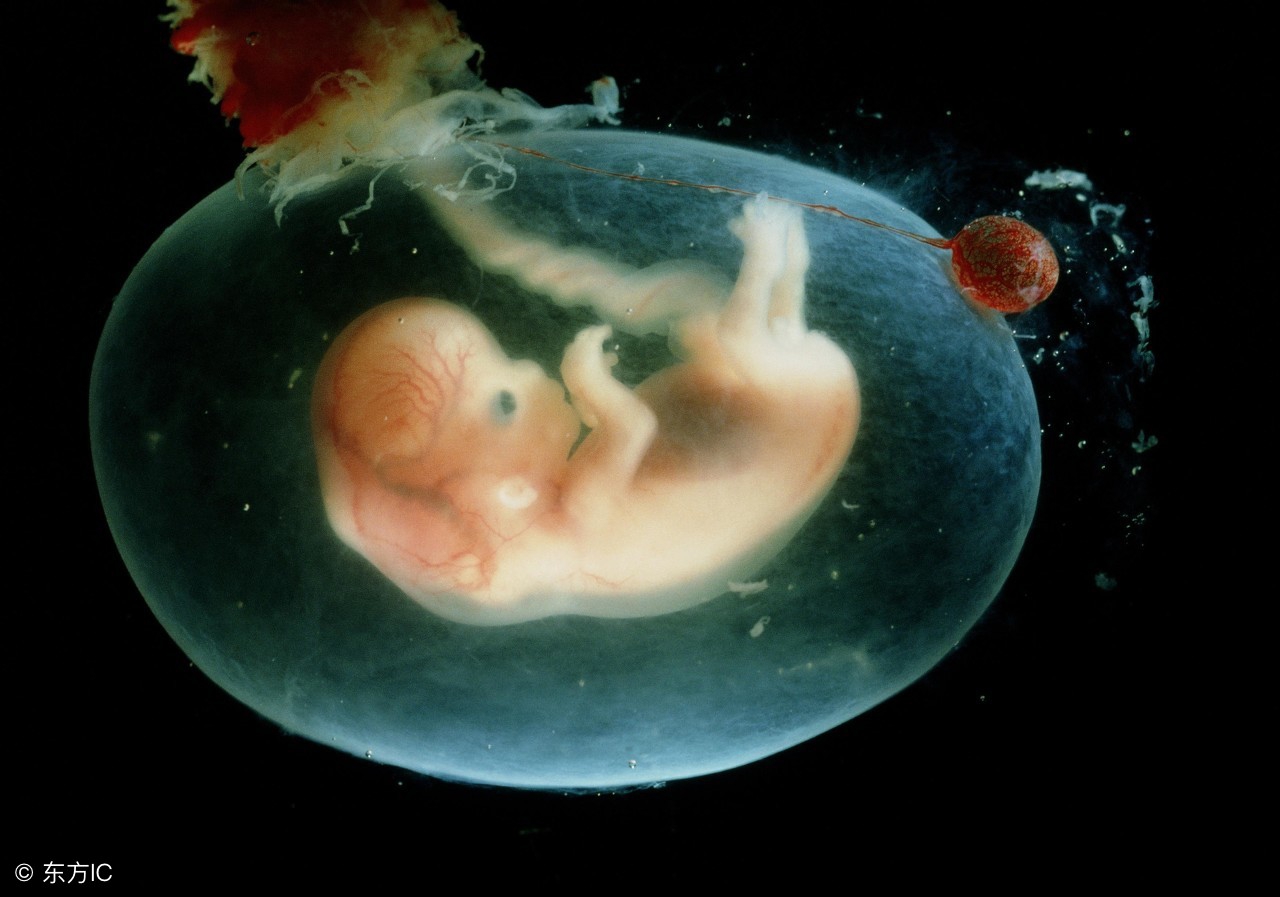

8周:胎儿长到1.66厘米,胎形已定,可分出胎头、体及四肢,胎头大于躯干。B超可见胎囊约占官腔1/2,胎儿形态及胎动清楚可见,并可看见卵黄囊。

9周:胎儿长到2.15厘米,胎儿头大于胎体,各部表现更清晰,头颅开始钙化、胎盘开始发育。B超可见胎囊几乎占满宫腔,胎儿轮廓更清晰,胎盘开始出现。

10周:胎儿长到2.83厘米,胎儿各器官均已形成,胎盘雏形形成。B超可见胎囊开始消失,月芽形胎盘可见,胎儿活跃在羊水中 。